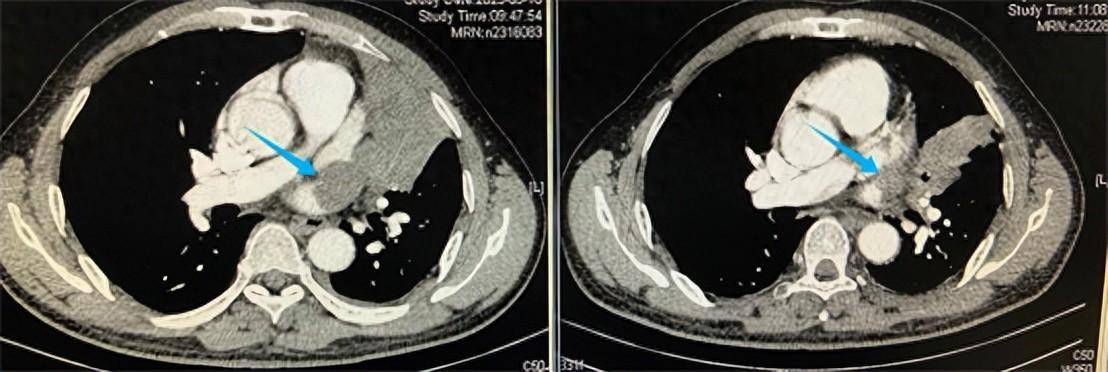

Đỉnh điểm là gần cảm lạnh gần nhất, uống thuốc cả tháng trời cũng không thấy đỡ, cả gia đình thuyết phục mãi chú Nguỵ mới chịu đi khám. Kết quả chụp CT và nội soi phế quản khiến cả nhà choáng váng: trong nửa phổi trên bên phải xuất hiện một khối u khổng lồ, thậm chí đã di căn và "nuốt chửng" một phần tim. Việc phẫu thuật cắt bỏ khối u gần như bất khả thi do kích thước lớn và vị trí nguy hiểm.

Khối u phổi của chú Nguỵ được thu nhỏ sau hơn 4 tuần điều trị (Ảnh BV cung cấp)

Gia đình đưa chú đi thăm khám nhiều nơi nhưng đều nhận kết luận khó phẫu thuật. Tại Bệnh viện Phúc Kiến (Trung Quốc), các bác sĩ đã chọn phương án kết hợp hóa trị và liệu pháp miễn dịch để thu nhỏ khối u trước khi tính tới phẫu thuật. Sau thời gian điều trị, khối u nhỏ lại đáng kể, song ca mổ vẫn tiềm ẩn rủi ro cao. Nhờ kinh nghiệm và kỹ thuật chuyên môn, ê-kíp phẫu thuật đã thành công loại bỏ khối u, nhưng bệnh nhân vẫn cần tiếp tục hóa trị và xạ trị bổ sung, đồng thời đối mặt nguy cơ tái phát.